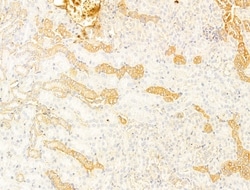

| Immunocytochemistry, Immunohistochemistry (Paraffin), Western Blot | |